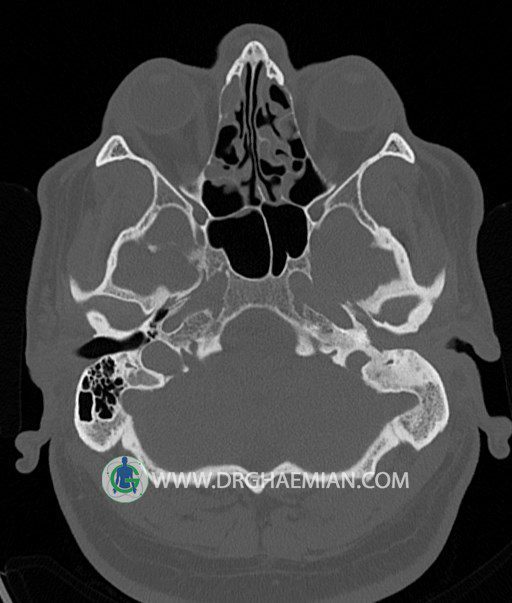

سی تی اسکن گوش داخلی به رادیولوژیست اجازه می دهد تا سطوح مختلف، یا اسلایس هایی از استخوان های که از جمجه به گوش می روند را از طریق امواج ایکس چرخشی مشاهده کند. در این کیس اودیت مدیا، ماستوئیدیت مزمن، اوتیت خارجی، انحراف سپتوم بینی، کونکا بولوزا و افزایش ضخامت سینوس ها مشاهده می شود.

در HRCT از استخوان تمپورال با مقاطع آگزيال ، ساژيتال و کرونال ظريف ( 0.6 mm ) :

– نماي کوکلهآي دو طرف با 2.5 دور گردش مجرا

– نماي cochlear aqueduct

– نماي semicircular canal خلفي ، لترال ، فوقاني و وستيبول

– استخوانچه هاي گوش داخلي شامل malleus ، incus و stapes (دنسيتي و رديف استخوانچه ها )

– نماي oval window و round window ، tympanic cavity ، attic و کانال گوش داخلي

– کانال عصب فاشيال و مسير ان از ناحيه کانال گوش داخلي ، geniculate ganglion تا محل خروج ان از stylomastoid foramen

– نماي tympanic membrane ، کانال ICA ، بولب جوگولار دو طرف

در حد طبيعي است .

– اپاسيتي گوش مياني چپ ناشي از وجود دانسيته نسج نرمي دراطراف استخوانچه ها همراه با اروژن اسکوتوم و

استخوانچه ها بدون جابجايي در رديف استخوانچه ها مشهود است که مطرح کننده اوتيت مديا همراه با نشانه

هاي مشکوک به کولستئاتوم مي باشد .

– اپاسيتي و اسکلروزيس ماستوئيد چپ نشانه ماستوئيديت مزمن

– اپاسيتي کانال گوش خارجي ناشي از دانسيتي نسج نرمي مطرح کننده external otitis

– انحراف سپتوم مياني بيني به راست

– کونکا بولوزا در کونکاي مياني چپ و

– افزايش ضخامت مخاطي در سينوس هاي اتموئيد و ماگزيلاري

اپاسيته